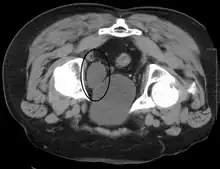

Cancer

Cancer of the bladder is known as bladder cancer. It is usually due to cancer of the urothelium, the cells that line the surface of the bladder. Bladder cancer is more common after the age of 40, and more common in men than women;[29] other risk factors include smoking and exposure to dyes such as aromatic amines and aldehydes.[29] When cancer is present, the most common symptom in an affected person is blood in the urine; a physical medical examination may be otherwise normal, except in late disease.[29] Bladder cancer is most often due to cancer of the cells lining the ureter, called transitional cell carcinoma, although it can more rarely occur as a squamous cell carcinoma if the type of cells lining the urethra have changed due to chronic inflammation, such as due to stones or schistosomiasis.[29]

Investigations performed usually include collecting a sample of urine for an inspection for malignant cells under a microscope, called cytology, as well as medical imaging by a CT urogram or ultrasound.[29] If a concerning lesion is seen, a flexible camera may be inserted into the bladder, called cystoscopy, in order to view the lesion and take a biopsy, and a CT scan will be performed of other body parts (a CT scan of the chest, abdomen and pelvis) to look for additional metastatic lesions.[29]

Treatment depends on the cancer's stage. Cancer present only in the bladder may be removed surgically via cystoscopy; an injection of the chemotherapeutic mitomycin C may be performed at the same time.[29] Cancers that are high grade may be treated with an injection of the BCG vaccine into the bladder wall, and may require surgical removal if it does not resolve.[29] Cancer that is invading through the bladder wall may be managed by complete surgical removal of the bladder (radical cystectomy), with the ureters diverted into a segment of part of ileum connected to a stoma bag on the skin.[29] Prognosis can vary markedly depending on the cancer's stage and grade, with a better prognosis associated with tumours found only in the bladder, that are low grade, that do not invade through the bladder wall, and that is papillary in visual appearance.[29]

Some forms of medical imaging exist to visualise the bladder. A bladder ultrasound may be conducted to view how much urine is within the bladder, indicating urinary retention. A urinary tract ultrasound, conducted by a more trained operator, may be conducted to view whether there are stones, tumours or sites of obstruction within the bladder and urinary tract. A CT scan may also be ordered.